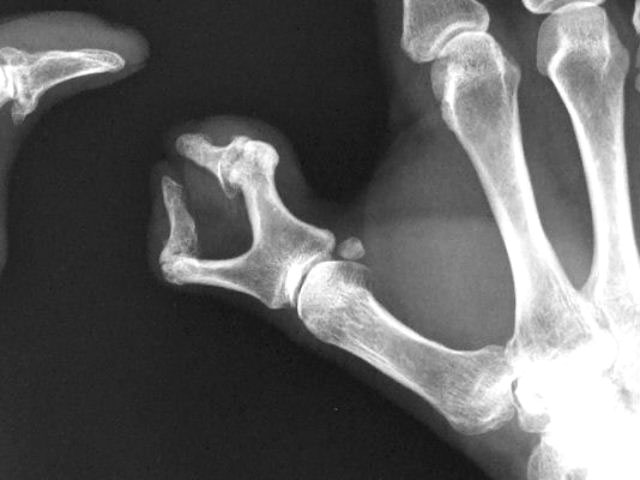

Artritis psoriásica y falange bífida.

Artritis psoriásica.

Falange distal de dedo 1º de mano, bífida.